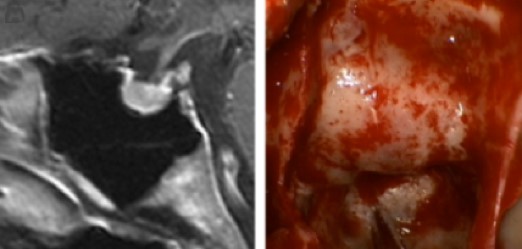

A tumor from this gland may secrete hormones excessively (even when <10mm, called Microadenoma) causing conditions like Acromegaly, Cushing’s disease, or infertility-related syndromes. Non-functioning tumors can grow and compress nearby structures, leading to vision problems or hormone deficiency. Many are detected incidentally during scans.